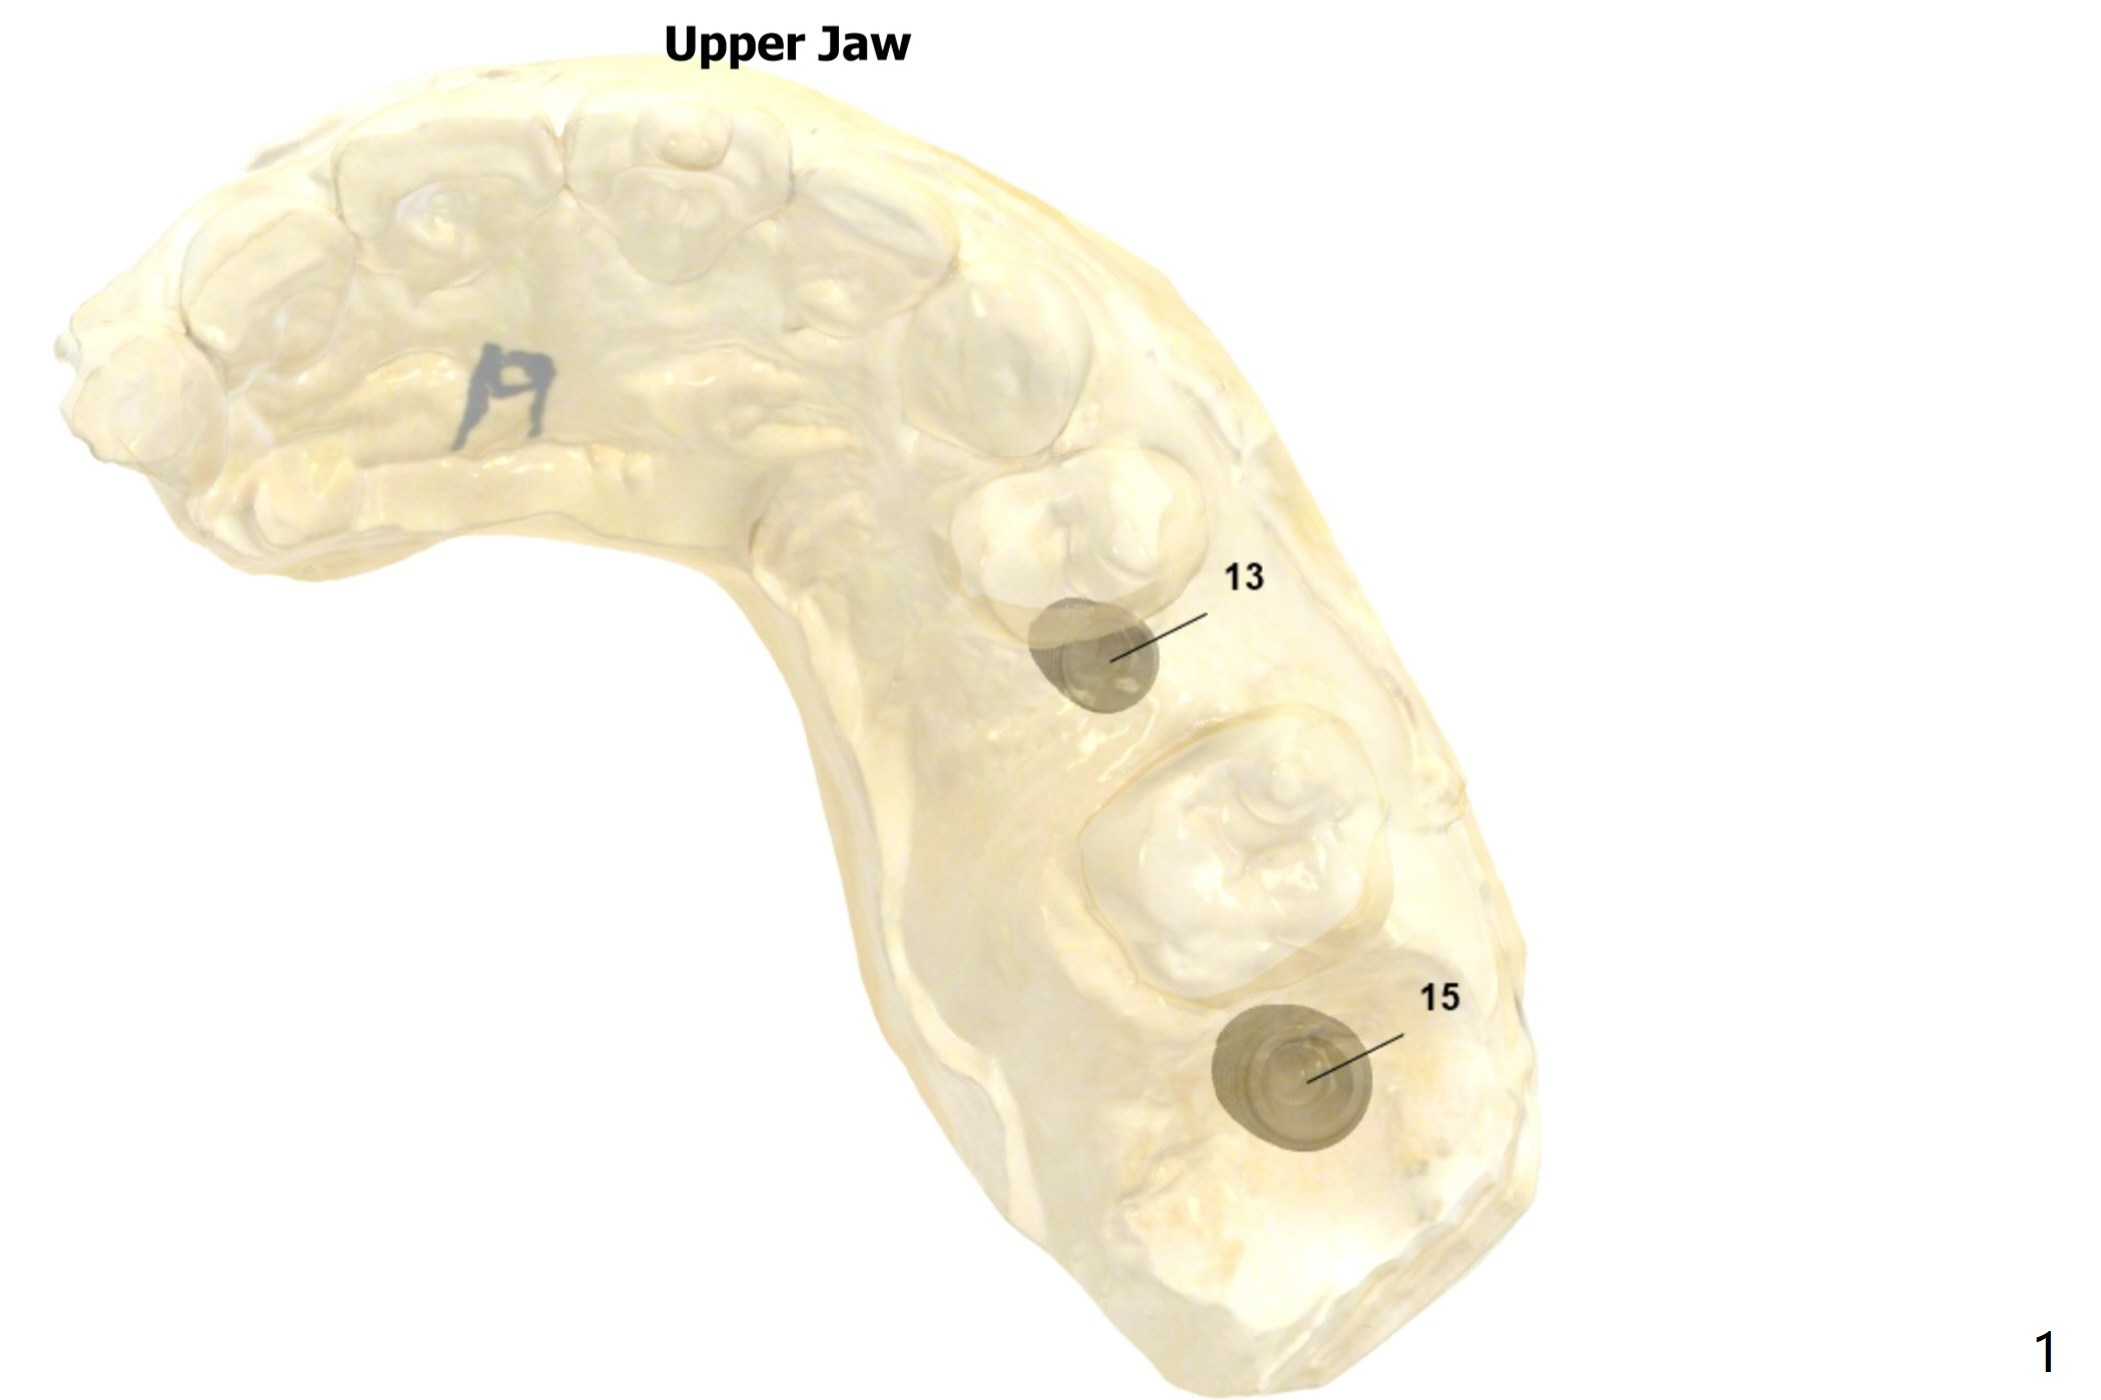

#13 Implant Mesial Placement

To close the diastema between #11 and 12 orthodontically, the implant at #13 will be placed slightly mesially.